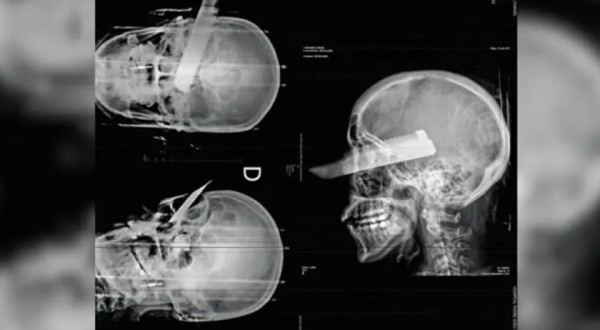

Mulher tem faca cravada no olho em tentativa de feminicídio no Oeste de SC Mulher tem faca cravada no olho em tentativa de feminicídio no Oeste de SC

Policial

Oeste de SC - Mulher tem faca cravada no olho em tentativa de feminicídio no Oeste de SC

Uma mulher sofreu uma tentativa de feminicídio na manhã desta segunda-feira (2) em São Carlos, no Oeste de Santa Catarina, ao ser atacada pelo companheiro dentro da residência ...